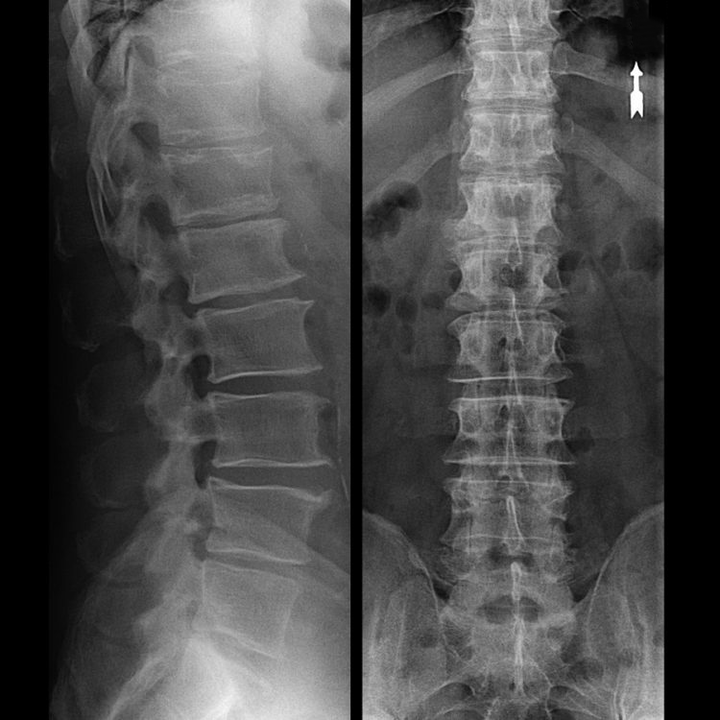

In typical cases, osteochondrosis of the cervical and cervical-thoracic spine manifests itself as described above.Therefore, the main stage of diagnosis was and remains the identification of the patient's complaints, establishing the presence of accompanying muscle spasm using a simple palpation of the muscles along the spine.Is it possible to confirm the diagnosis of osteochondrosis with an X-ray examination?

An "X-ray" of the cervical spine and even functional tests of flexion and extension do not show cartilage because their tissue transmits X-rays.However, based on the location of the vertebrae, general conclusions can be drawn about the height of the intervertebral discs, the general straightening of the physiological curvature of the neck - lordosis, as well as the presence of marginal growths of the vertebrae with prolonged irritation of their surfaces by fragile and dehydrated intervertebral discs.Functional tests can confirm the diagnosis of instability in the cervical spine.

Since the discs themselves can only be seen with CT or MRI, magnetic resonance and X-ray computed tomography are indicated to clarify the internal structure of the cartilage and formations such as protrusions and hernias.Thus, with the help of these methods, an accurate diagnosis is made, and the result of the tomography is an indication and even an up-to-date guide for operative treatment of hernia in the neurosurgery department.

- You can regularly take at least an x-ray of the lumbar spine in two projections or an MRI to find out if the hernia is progressing, if any;